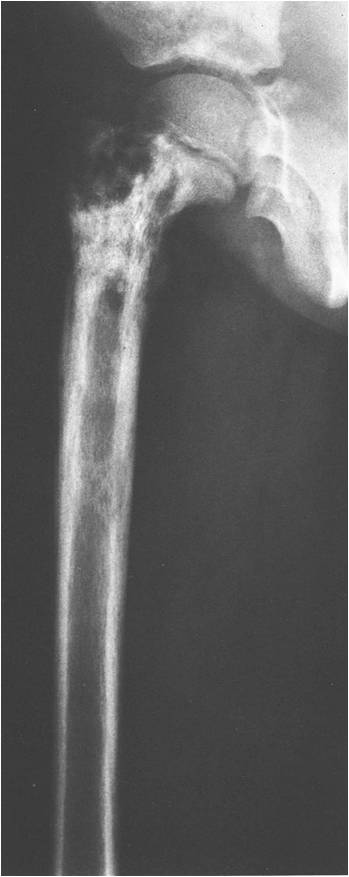

Permeative Lesion

- Permeative or moth eaten bone destruction (55%)

- Geographic (11%); Blow out (1%); Blastic (2%); Normal XR (5%)

- Metadiaphysis (75%)

- Periosteal reaction—may look benign

- Lower extremities involved most often especially femur and pelvis